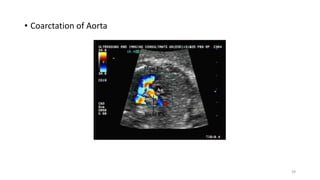

• Coarctation of Aorta